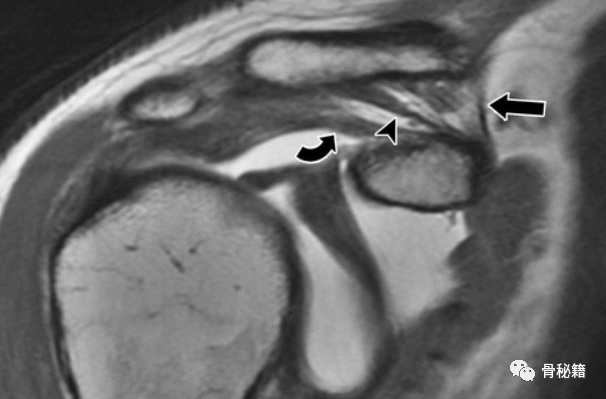

男性喙突韧带的正常解剖结构。右肩浅斜冠状 T1 加权 MR 关节造影显示正常韧带起源于喙突。喙肩韧带(弯曲的箭头)位于最外侧,以浅角度向肩峰延伸。在喙肩韧带内侧,CC韧带的梯形部分(箭头)插入锁骨外侧的下缘。锥形韧带(直箭头)位于梯形的后内侧,具有垂直方向的纤维,连接到距关节一定距离的锁骨下后缘。